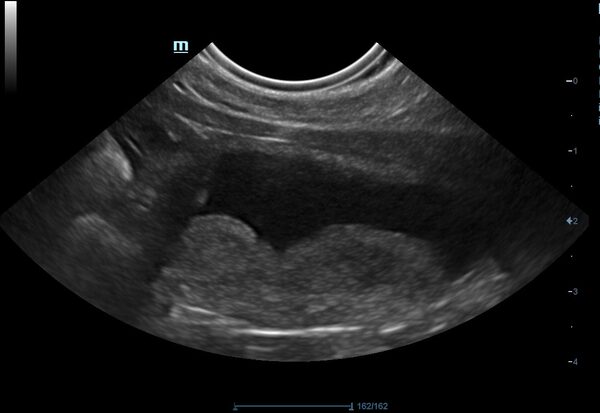

Tiger ist inzwischen ein 17-jähriger Europäisch-Kurzhaar-Kater. Letztes Jahr wurde er uns im Sommer wegen chronischer Magen-Darm-Beschwerden und Gewichtsverlusts vorgestellt. Trotz seines Alters scheuten seine Besitzer keine Kosten und Mühen. Im Ultraschall zeigten sich eine verdickte Darmwände, besonders die Muskelschicht war sehr dick (rote Markierung). Um der Ursache auf den Grund zu gehen, entnahmen wir Gewebeproben. Von dem Eingriff erholte sich Tiger sehr gut und die Wunden heilten ab.

Leider ergaben die Proben, dass es sich um einen Tumor handelte.

Aber Tigers Besitzer waren wieder bereit, alles für Tiger zu tun. Er bekommt seitdem eine Chemotherapie in Tablettenform und Kortison gegen die Entzündung.

Nun war Tiger zu einer Kontrolluntersuchung bei uns und es geht ihm blendend.

Im Ultraschall ist deutlich zu sehen, dass die Darmwand nicht mehr verdickt und der Tumor unter Therapie derzeit unter Kontrolle ist.